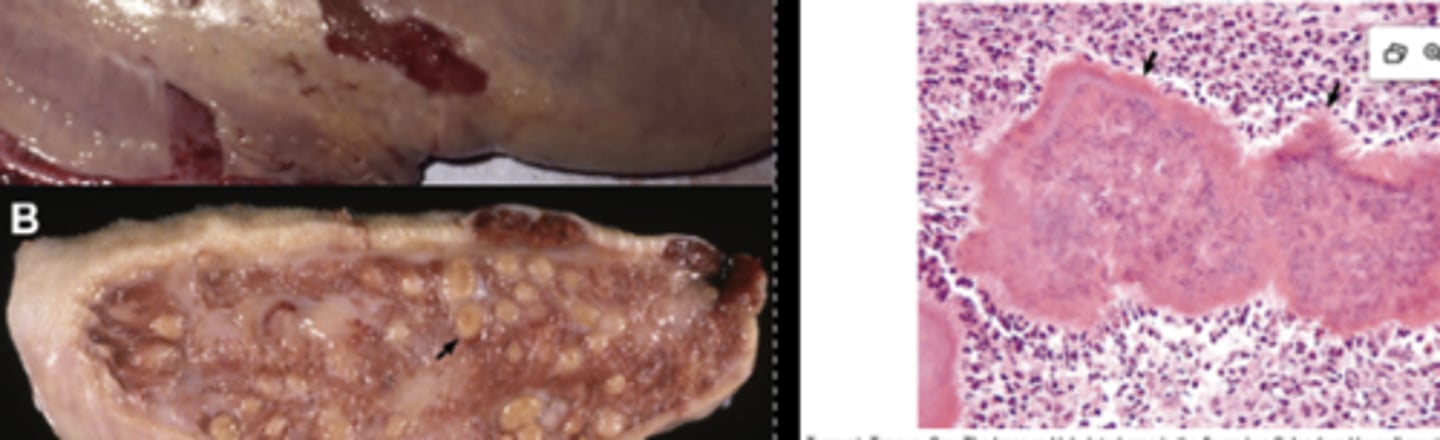

BLV Lymphoma

-nodular

What has caused this gross appearance of this bovine liver?

What has caused the gross appearance of this bovine liver?

BLV